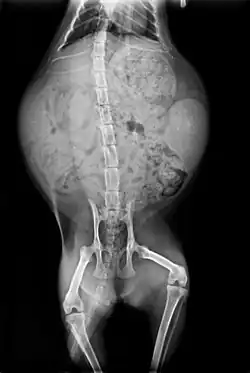

Skeleton

Cats have seven cervical vertebrae (as do most mammals); 13 thoracic vertebrae (humans have 12); seven lumbar vertebrae (humans have five); three sacral vertebrae (as do most mammals, but humans have five); and a variable number of caudal vertebrae in the tail (humans have only three to five vestigial caudal vertebrae, fused into an internal coccyx).[51]: 11 The extra lumbar and thoracic vertebrae account for the cat's spinal mobility and flexibility. Attached to the spine are 13 ribs, the shoulder, and the pelvis.[51]: 16 Unlike human arms, cat forelimbs are attached to the shoulder by free-floating clavicle bones which allow them to pass their body through any space into which they can fit their head.[52]